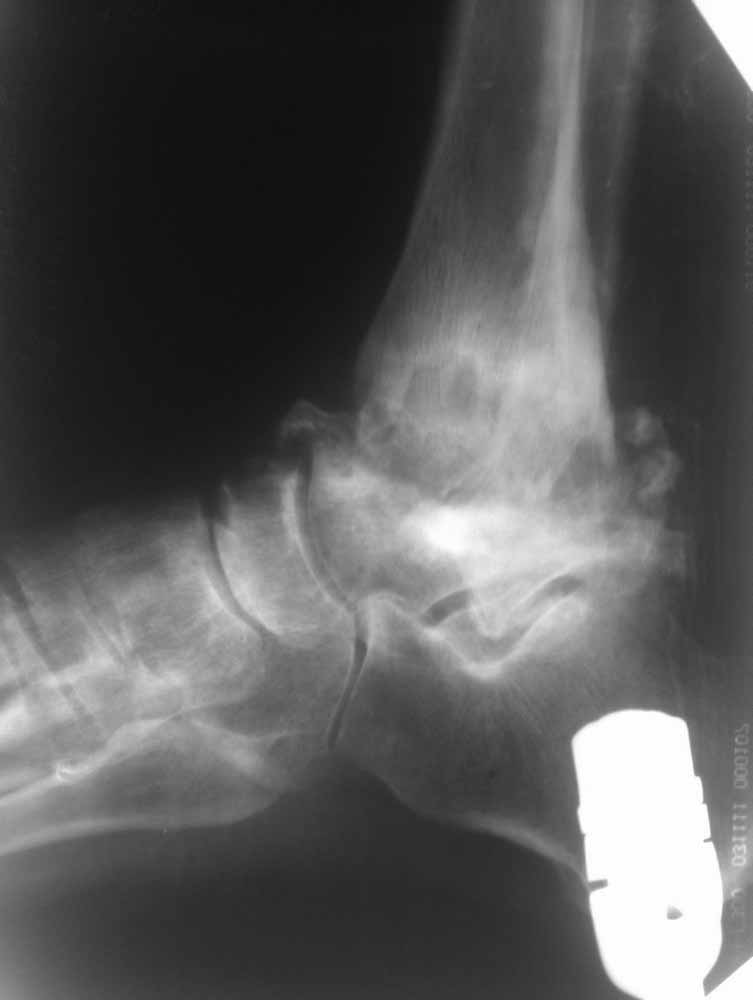

Опять прошу прощения за качество фото, но принципиальные моменты мне кажется, что видны.

Из того, что я вместе с лучевыми диагностами разглядел - нельзя исключить остеомиелит (?) - есть краевая реакция, куча элементов, похожих на секвестры. Смущает полное отсутствие местной и системной реакции - к анализам не придраться.

Про оперативное - думаем об артродезе правого голеностопа (пока и там ничего не съехало - боль в правом голеностопе усилилась из-за увеличения нагрузки), а слева (где как раз и есть некроз тарана и пилона) - открыть, чистить, бусы с антибиотиком, максимально коррекция сразу + аппарат.

Про опухоли - склоняюсь к мысли, что все таки может быть какое-то из последствий лучевой болезни (31 явка на ЧАЭС) (?!)...

Наверное здесь имеется асептический некроз таранной кости с патологическим внутренним подвывихом стопы на фоне подагрической артропатии.

Склоняемся к мысли, что все таки Charcot's Joint.

Прогрессивное разрушение скелета и характерную деформацию можно увидеть при нейропатической артропатии или Charcot arthropathy.